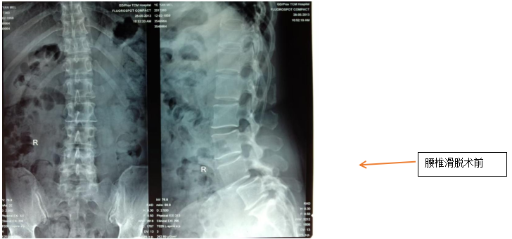

經皮微創置釘脊柱融合術手術與非融合手術

融合術:適用于腰椎管狹窄、腰椎滑脫等需穩定脊柱的病例;

非融合術:主要用于脊柱骨折等短期固定需求。

兩種術式均通過經皮置入椎弓根螺釘,避免傳統開放手術對腰背肌肉的大范圍剝離,具有出血少、疼痛輕、康復快等優勢。

腰椎滑脫手術復位固定